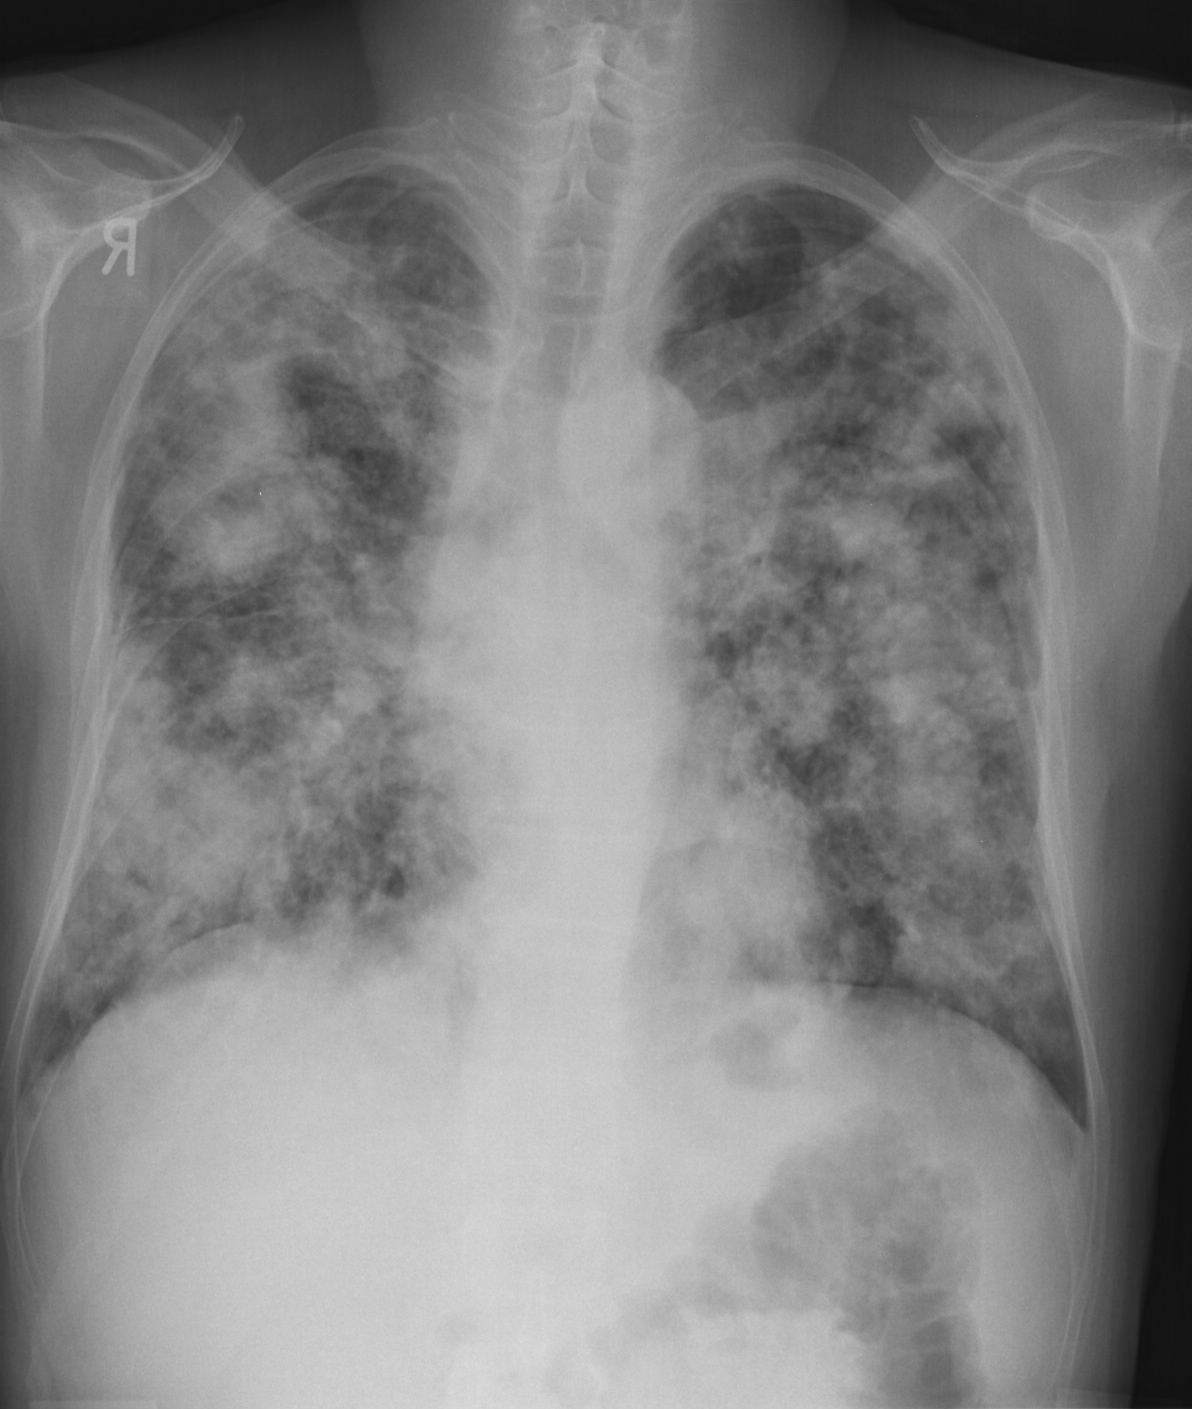

3a: Round shadow: multiple lung metastasis. Chest radiograph (PA)

Radiograph: Bilateral extensive, confluating patchy-nodular shadowing with diffuse reticular pattern. The diaphragm contour is partially blurry bilaterally: lymphangiosis carcinomatosa.

CT: Numerous 1-6 cm round and irregular, lobulated-spiculated contrast enhancing lesions in both lungs, everywhere sporadically.